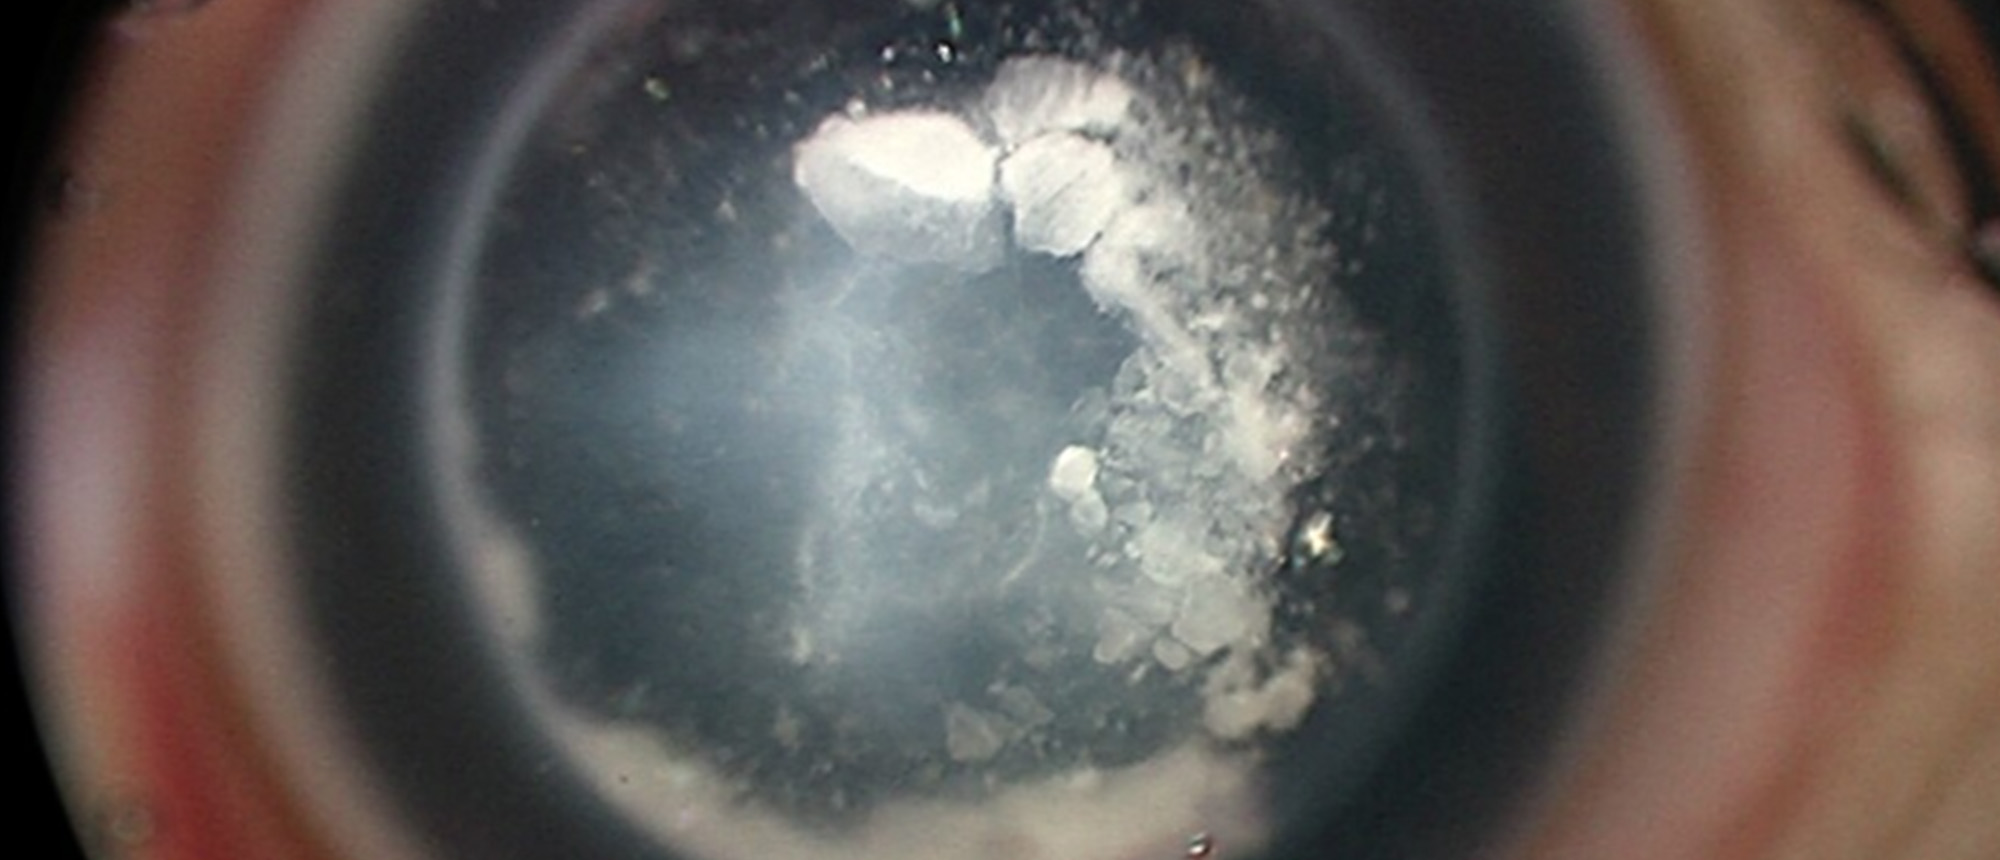

An infant was referred into Bascom Palmer for congenital corneal opacity in the right eye. Exam in clinic is notable for corneal opacity with what appears to be lens material in the anterior chamber and calcific changes of the lens. Exam under anesthesia revealed lens adherent to the posterior cornea and a diagnosis of type II Peters anomaly was made. To prevent deprivational amblyopia, the lens material was surgically removed. Penetrating keratoplasty nor optical iridectomy were deemed necessary in this case. Posterior exam revealed retinal pigmentary changes. Genetic testing revealed a pathogenic variant in NR2E3, associated with enhanced S-cone syndrome. To our knowledge, this is the first case of possible enhanced S-cone syndrome co-occurring with Peters anomaly.